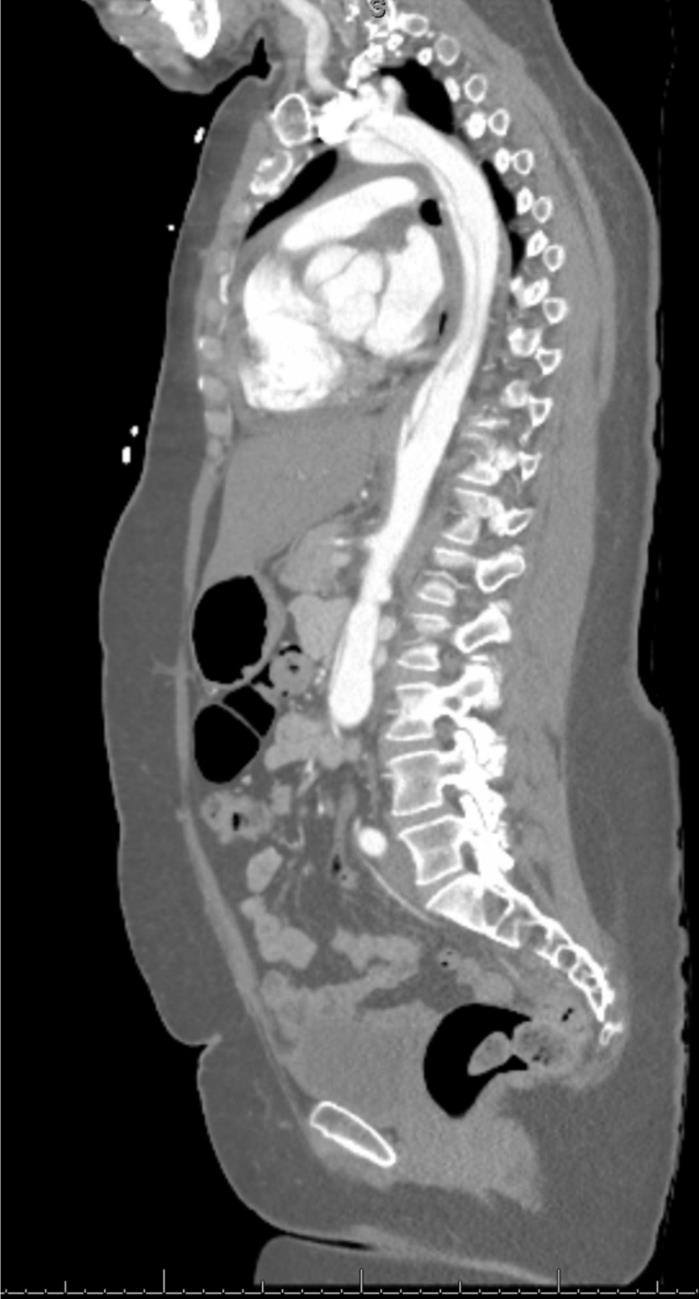

GORE_Figure3